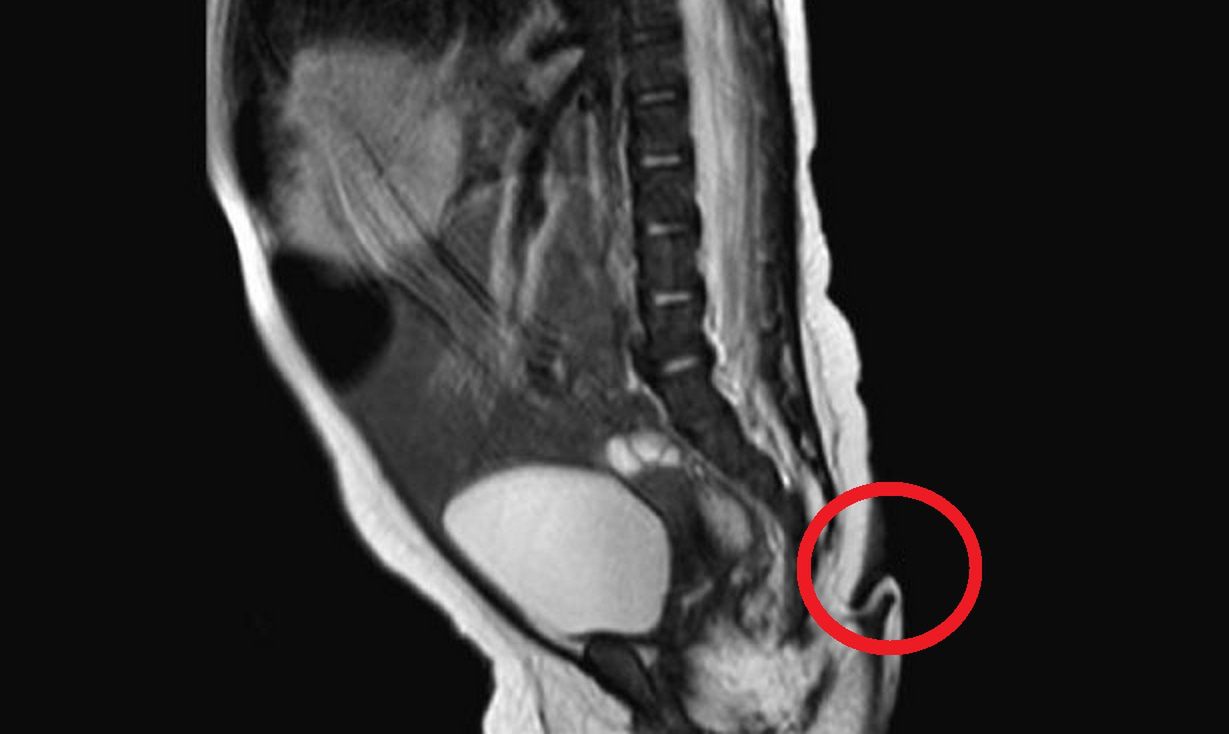

U dziewczynki znaleziono dużego guza w kręgosłupie, który atakował także układ trawienny, przez co miała problemy z jelitami. Rodzice usłyszeli, że małej Rose pozostało jedynie kilka tygodni życia. Zmarła w dziecięcym hospicjum dwa dni po swoim pierwszych urodzinach.